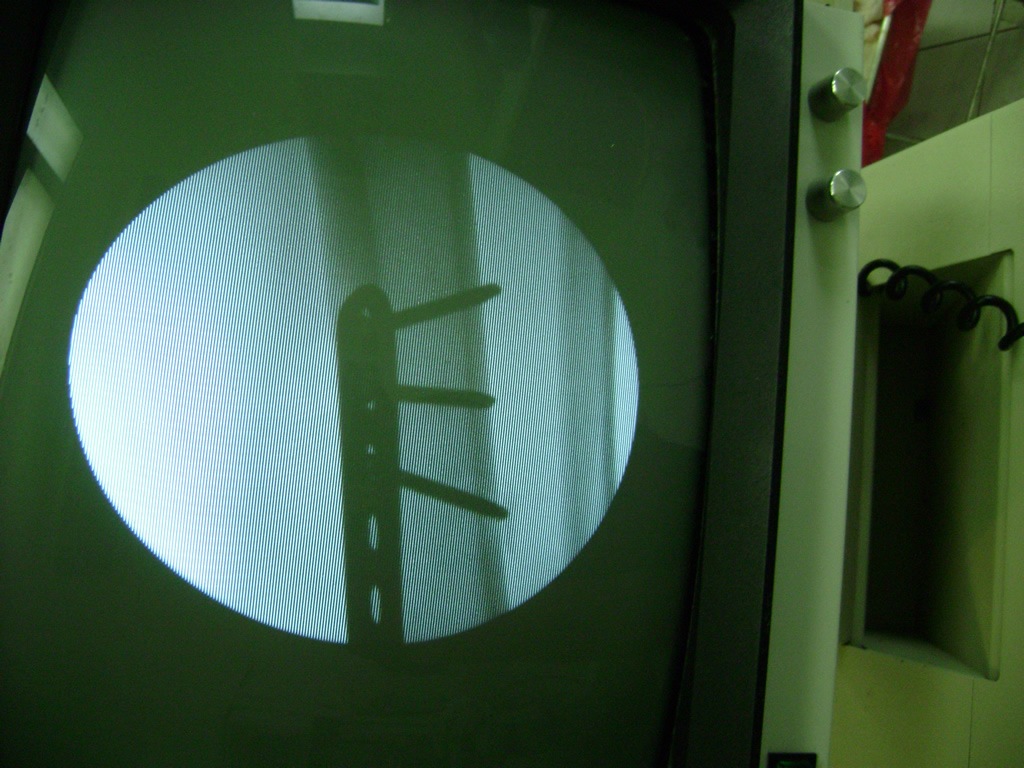

Cirugías de Tobillos

Debido a la fina cobertura de piel que recubre la tibia y el peroné, las fracturas generalmente son abiertas, es decir, el hueso roto rasga la piel, atravesándola. Las fracturas de tibia y peroné generalmente se producen por un fuerte impacto o torsión.

De esta forma nos ponemos a tus órdenes, somos conocedores de estos tipos de problemas, visitarnos será un gusto el poderte ayudar. cualquier inquietud puedes escribirnos al correo Esta dirección de correo electrónico está siendo protegida contra los robots de spam. Necesita tener JavaScript habilitado para poder verlo.